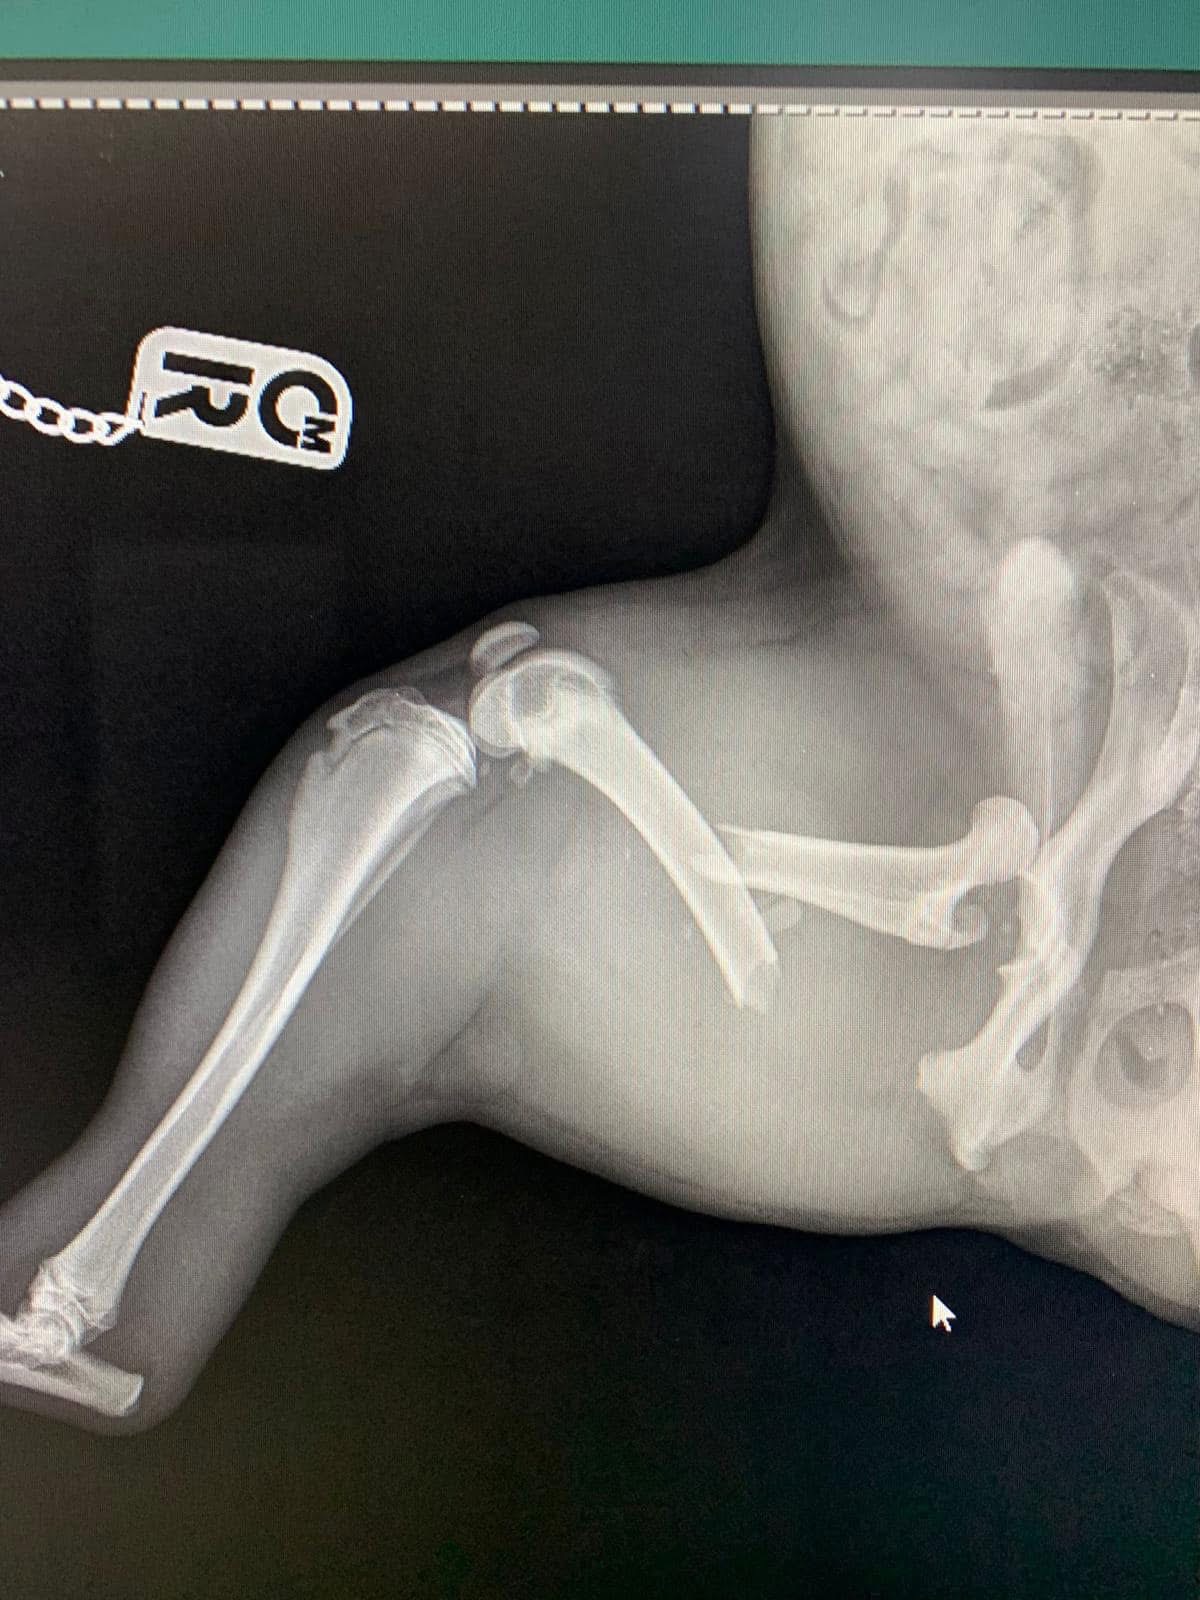

- Liječenje prijeloma kostiju, uključujući intraartikularne frakture

- Hirurške intervencije na zglobovima(artrotomija, artrodeza)

- Korektivne osteotomije za ispravljanje deformiteta